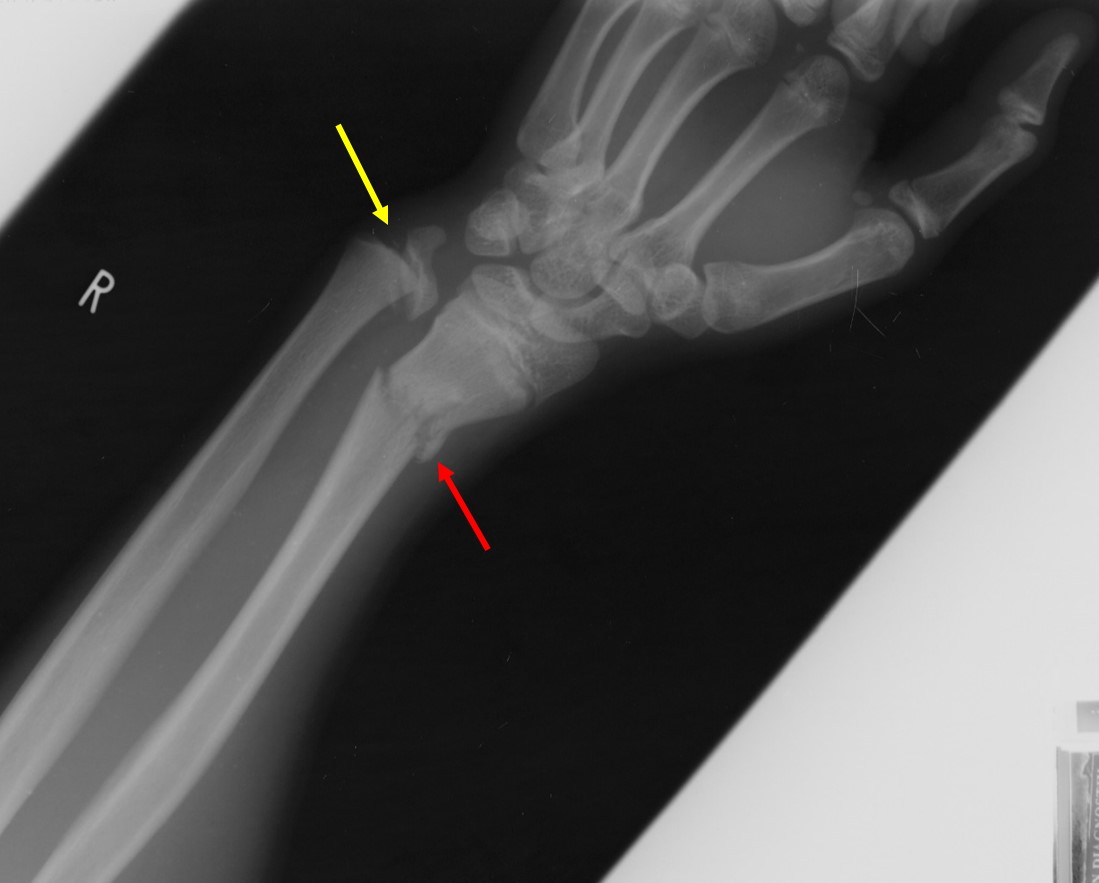

From brownemblog.com

Distal Radius Fractures — BROWN EMERGENCY MEDICINE Old Bone Fracture Radiology The images are of a patient with a typical bamboo spine as a result of ankylosing spondylitis. The fracture hematoma initiates the healing response. The bone is usually very osteoporotic. Within 48 hours, chemotactic signaling mechanisms attract the inflammatory. Some of these missed diagnoses are followed by excellent functional recovery, and later only radiographic deformities can be found as. Patients. Old Bone Fracture Radiology.